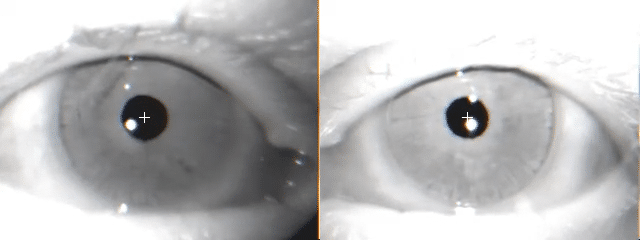

In the majority of your bedside exams, you are actively looking for this very saccadic eye motion. The HIT specifically assesses the high-frequency function of the VOR. Consider a patient with a right unilateral vestibular hypofunction (RUH):

When you perform a rapid head impulse to the right, you activate the impaired right horizontal semicircular canal. Because the right ear is damaged, it cannot produce the necessary robust excitatory response to that rapid head turn. Its signal output is weak, failing to match the speed of the head movement. Consequently, your patient's vestibulo-ocular reflex (VOR) for rightward head movements is deficient, characterized by a reduced VOR gain (i.e., eye velocity/head velocity ratio). Their eyes cannot maintain fixation and instead slip off target, moving with the head to the right. As the eyes slip, the brain detects the visual error and fires off a repositioning saccade (a catch-up saccade, the fast phase of the nystagmus) to bring the eyes back to the target. Since the eyes slipped to the right, this corrective saccade returns to the left, which is the direction of the more neurally active (healthy) ear.

This observation, the presence of that particular saccade, is a positive HIT and unequivocally points to a right-sided vestibular deficit. This repositioning saccade is your central nervous system's visible attempt to compensate for the peripheral failure, and its presence indicates a significant VOR impairment to the side of the head thrust. It is the core finding you seek. Note that while overt saccades are visible, more subtle covert saccades can also occur during the head movement, also indicating a VOR deficit.

When you perform a rapid head impulse on a patient with a healthy vestibular system, their VOR functions perfectly. Their eyes maintain a stable gaze on the target throughout the rapid head movement, equally and oppositely moving to the head. This means their brain receives balanced and appropriate signals from both inner ears, allowing for seamless gaze stabilization. In this scenario, you observe no corrective repositioning or catch-up saccades. This absence of saccades is precisely what you look for to confirm normal VOR function.